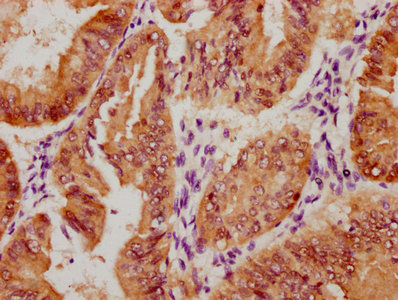

The image on the left is immunohistochemistry of paraffin-embedded Human thyroid cancer tissue using CSB-PA919263(SPAG4 Antibody) at dilution 1/25, on the right is treated with synthetic peptide. (Original magnification: ×200)